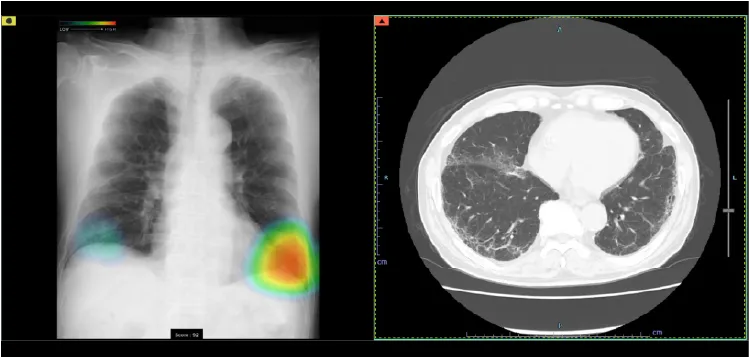

CTは Computed Tomography(コンピュータ断層撮影) の略で、X線を使って体の断面を撮影する装置です。体の内部構造を詳しく画像化できるため、さまざまな病気の発見に役立ちます。近年の技術進歩により、0.5mm間隔で断層画像を撮影できるため、ごく小さな病変も見つけることが可能になりました。また、得られた断面画像を重ね合わせることで、立体的な3D画像を作成することもできます。さらに、必要に応じて 造影剤 を使用すると、腫瘍などの病変部位がより明瞭に写り、周囲の血管の走行や栄養血管の状態を詳しく把握することができます。ただし、造影剤には副作用の可能性があり、また腎機能が著しく低下している場合には使用できないことがあります。造影剤を使うかどうかは、検査内容に応じて医師が判断します。

当院ではGE社製の64列マルチスライスCTを導入しています。被ばく低減可能な逐次近似画像構成法ASiR-VソフトウェアやAI技術を駆使した次世代ワークフローを搭載した最新のCTで検査が行えます。